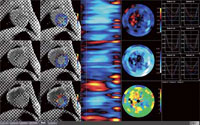

MR遅延造影解析

遅延造影撮像のデータから,心筋梗塞領域の位置と範囲を表示し,Bull’s eye mapで局所の心筋バイアビリティを評価することができる。ワンクリックで外膜側,内膜側をオートトレースする。遅延領域の面積と体積を自動計測し,全心筋,内膜側,外膜側のBull’s eye mapが表示される。